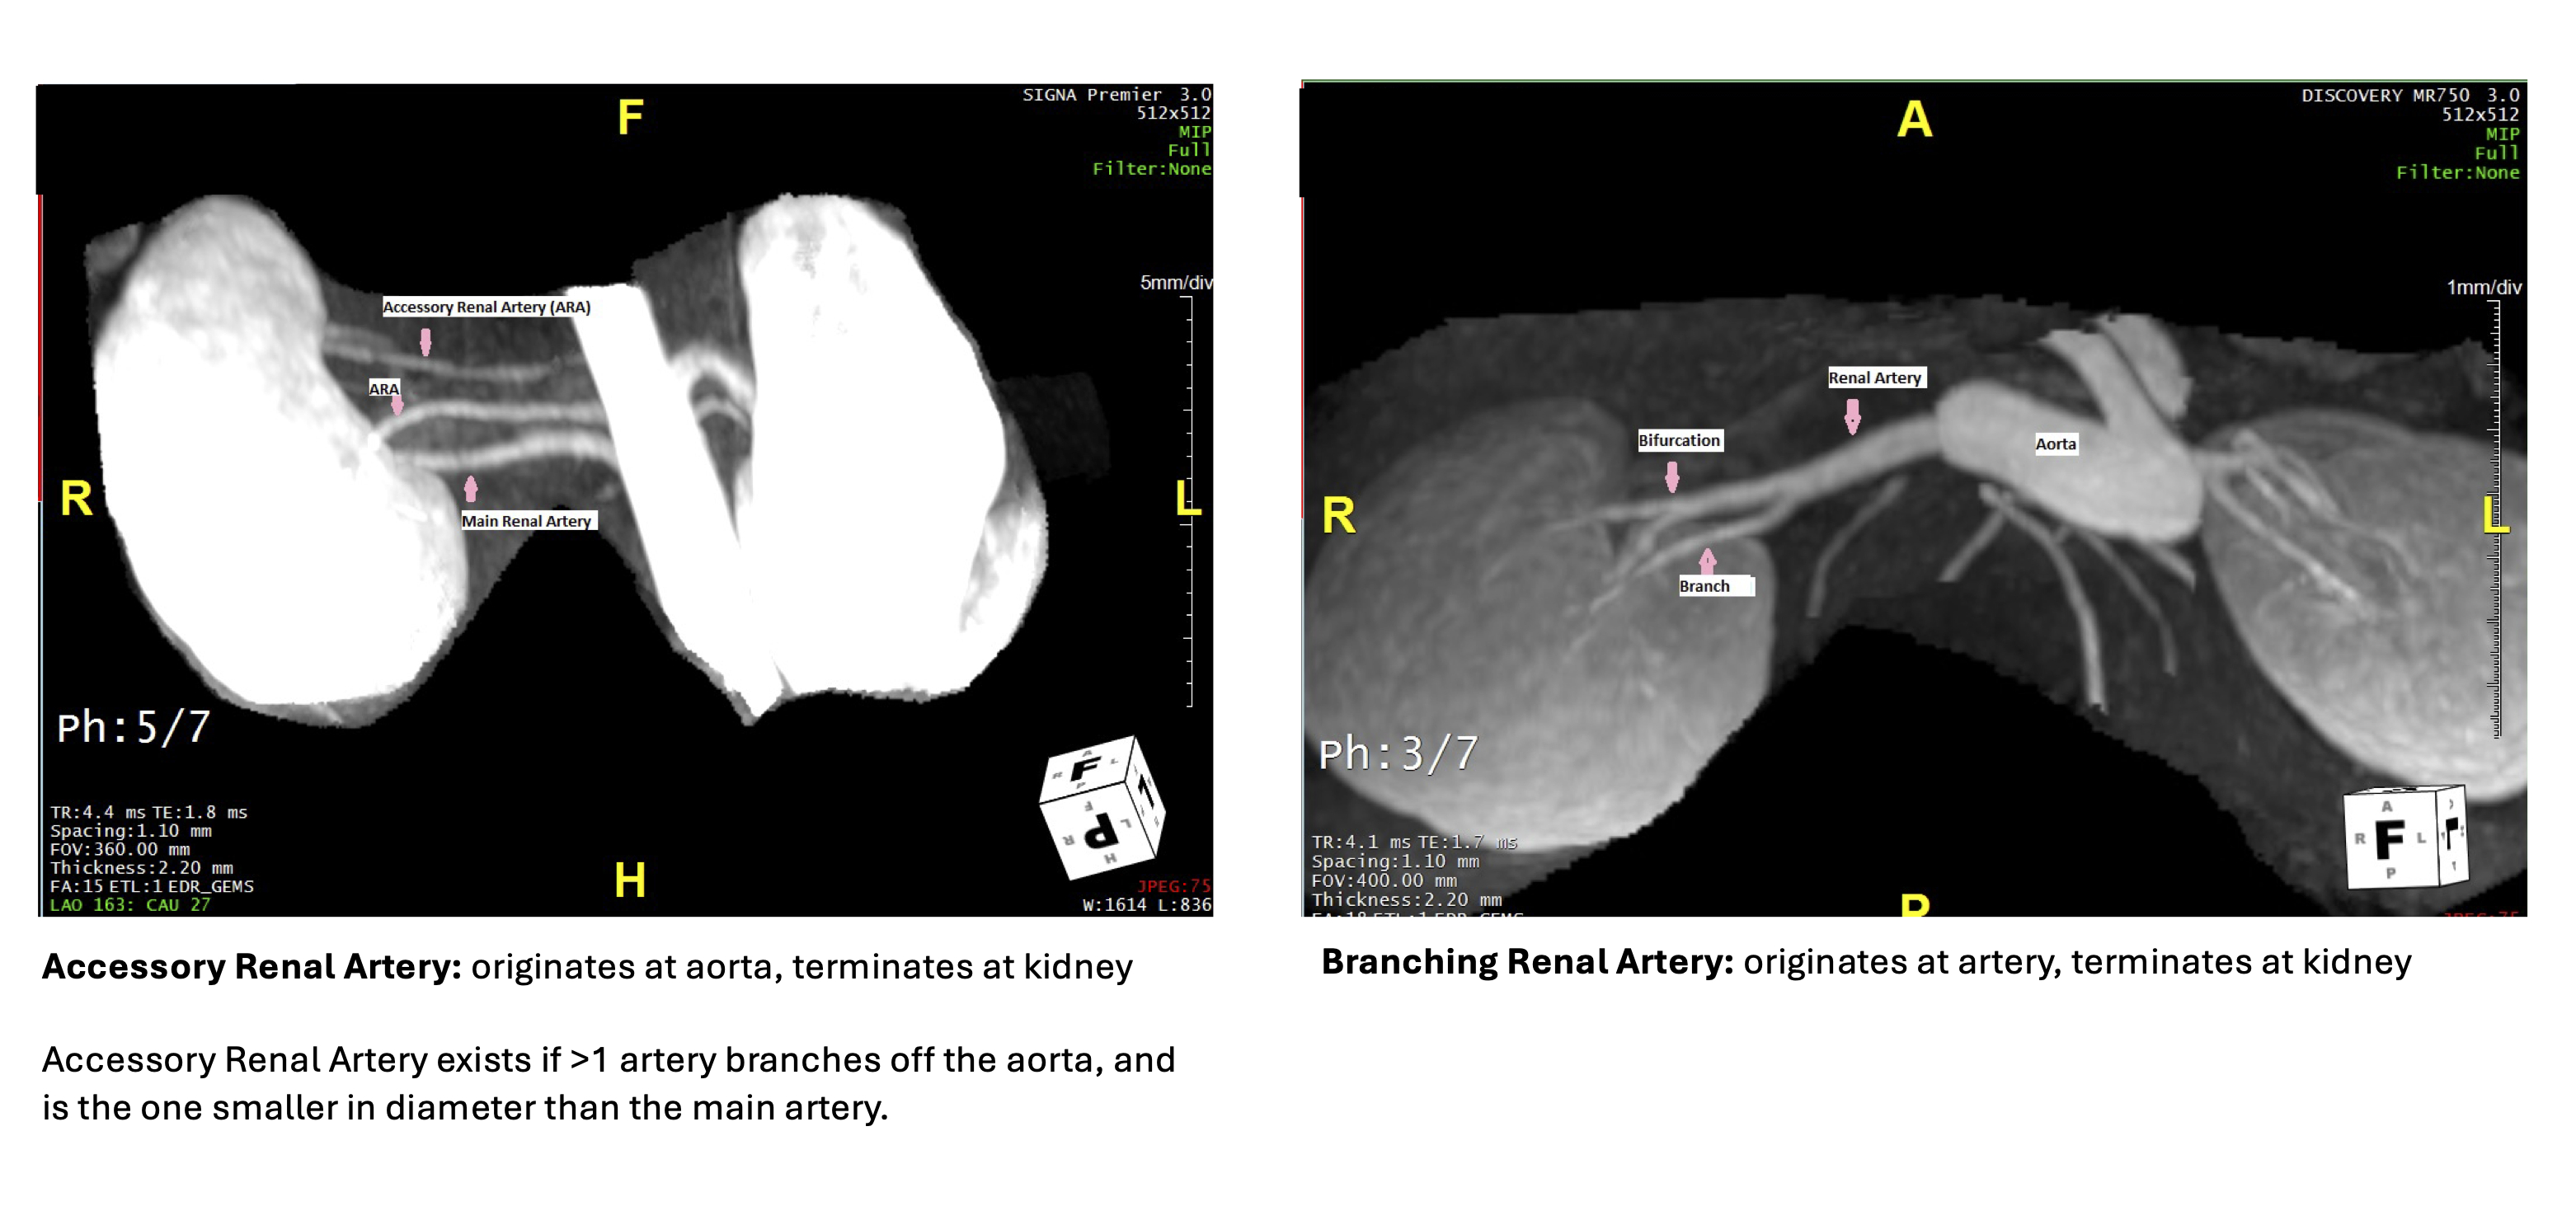

Abstract Body: Introduction: Renal accessory arteries originate at the aorta and deliver renal blood flow independent of the main renal artery, while renal artery branches originate from and their flow depends on the main renal artery. However, the clinical significance of accessory arteries remains unclear. We tested the hypothesis that characteristics of renal accessory and/or branching arteries morphology are linked to resistant hypertension (RH).

Methods: In a case-control study we compared the presence and characteristics of renal accessory and branching arteries (exposures) in individuals with RH (cases) vs. healthy kidney donors (normotensive controls) (Figure 1). Using MR angiography we calculated the length, diameter, tortuosity, and resistance (8*Length*blood viscosity)/(πr4)) of each artery (Figure 2). In separate logistic regression analyses we compared cases and controls for each of the following accessory or branching artery parameters: number of vessels, smallest diameter, length of longest vessel, greatest tortuosity, and greatest resistance.